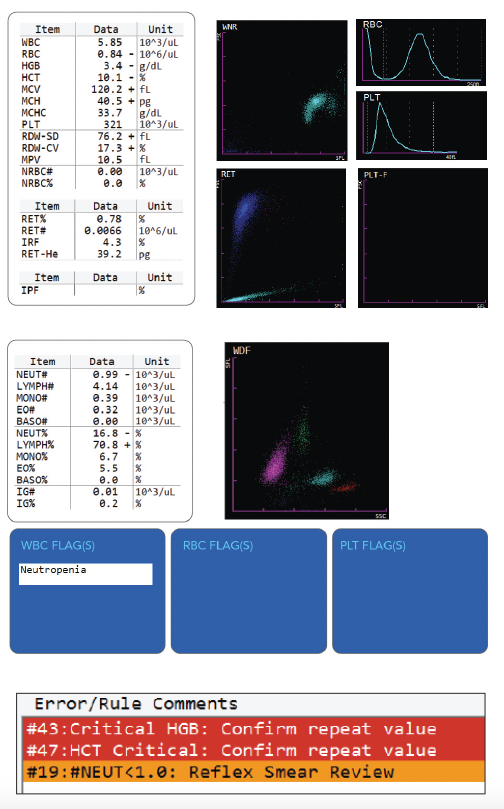

This sample (see PDF) was drawn from a 2 year old patient presenting to the pediatrician with pica (consumption of non-nutritive substances). The initial CBC results led to the patient being redrawn per lab policy; the redraw confirmed the original values. The combination of a markedly decreased RBC, HGB, HCT and reticulocyte count in conjunction with the increased MCV led to an eventual diagnosis of Diamond-Blackfan Anemia (DBA).

Diamond-Blackfan Anemia is a congenital erythroid aplasia that usually presents within the first 1-2 years of life. The disorder is thought to be caused by a defect in erythroid precursor cells that results in early cell death and subsequent failure of the bone marrow to produce red blood cells. Oftentimes, DBA patients also have facial or skeletal abnormalities, depending on the severity of the disease. DBA can be distinguished from Fanconi’s anemia (which causes bone marrow aplasia) by the normal, or near-normal, WBC and platelet counts.